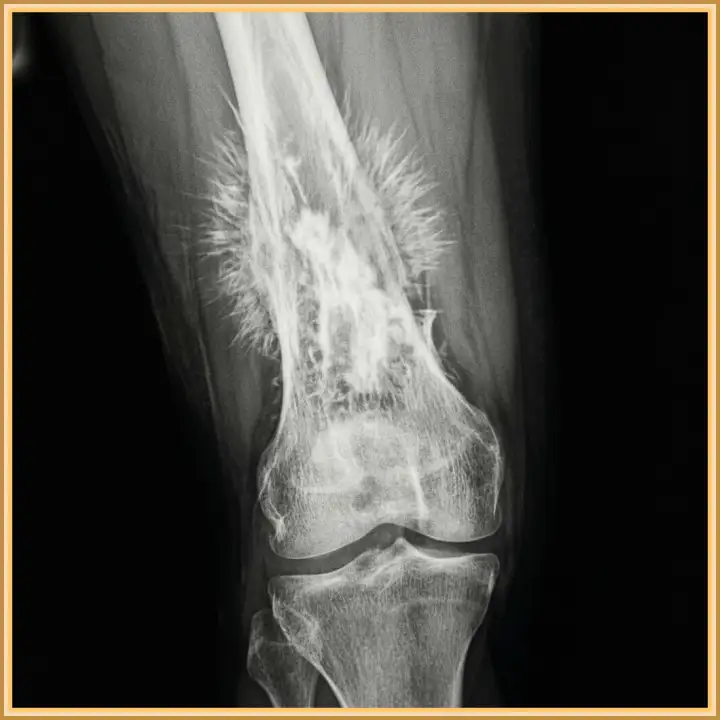

На снимке — кость, разрушенная остеосаркомой. Самый пугающий и одновременно крайне показательный признак здесь — так называемые спикулы, или игольчатый периостит. Видите торчащие острые «лучи», похожие на ежиные иголки? Это не случайное совпадение. Такая картина — не просто деталь, а важнейший маркер стремительного роста злокачественной опухоли, которая молниеносно врастает в соседние ткани, создавая хаотичные костные наросты.

Для специалистов по онкологии и рентгенологов подобная картинка на снимке — не просто заключение, а тревожный звоночек, требующий мгновенной реакции. Игольчатый периостит зачастую говорит о высокой злокачественности новообразования и его быстром прогрессе. Каждый потерянный день здесь может стать решающим. Это гонка на время, на кону которой — человеческая жизнь.